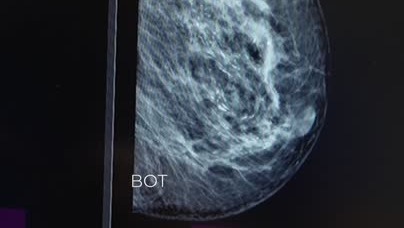

У пациентки 61 года обнаружили в левой молочной железе множественные микрокальцинаты. Продолжение ролика

В России растет число пациенток с РМЖ — каждый год в стране диагностируют около 85 тыс. новых случаев. Врачи объясняют это поздними родами или полным отказом от деторождения, приемом гормональных препаратов, высоким уровнем стресса и нездоровым образом жизни. Свою роль играют и наследственные мутации в некоторых генах. «Известия» выяснили, как диагностировать болезнь на ранней стадии, чтобы максимально повысить шансы на выздоровление. В России растет число пациенток, страдающих раком молочной железы...